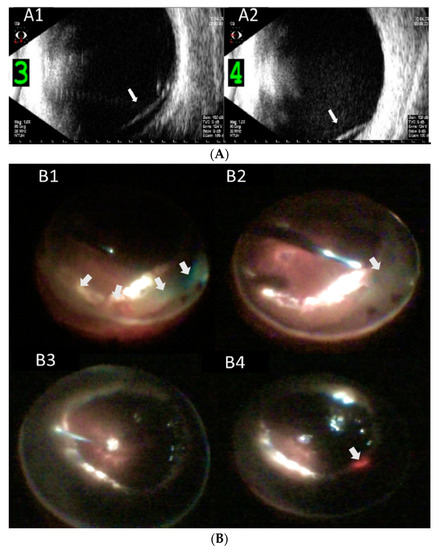

| 3 | 46 | M | R | 0.05 (1.3) | 39 | - | + | - | PPV*2, SB + SO + PPL | Aphakia | 26 | 270° retinectomy + SO refill | 225° pRD | + | 6 | 0.1 (1.0) | WNL | |

| 4 | 40 | M | R | 0.025 (1.6) | WNL | - | + | - | PPV*1, SB + SO + PPL | Aphakia | 22 | 180° retinectomy + PI + SO refill | 180° pRD | - | 22 | 0.05 (1.3) | WNL | |